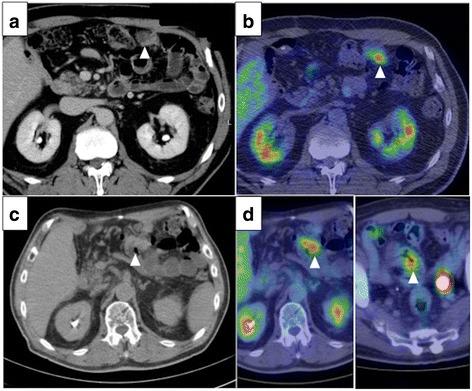

A 61-year-old man diagnosed with HCCA was referred to our hospital. We performed an extended left hemi-hepatectomy and caudate lobectomy with extrahepatic bile duct resection. The tumor stage was T2aN0M0, stage II, based on the TNM classification, seventh edition. R0 resection was successfully performed. Adjuvant chemotherapy was not administered. After 38 months, computed tomography revealed peritoneal dissemination. The patient received chemotherapy with tegafur-gimeracil-oteracil-potassium (S-1) and gemcitabine. The peritoneal dissemination was successfully controlled for more than 50 months. During the treatment, levels of CEA and CA19-9 kept rising slowly, which was followed by bowel obstruction due to peritoneal dissemination of HCCA. The patient underwent resection of transverse colon with tumor nodules, and the tumor was pathologically diagnosed as metastasis of HCCA. Tumor markers decreased to normal levels, and the patient has been free from tumor relapse for 6 months.

一名61岁被诊断为HCCA的男性患者被转诊至我院。我们实施了扩大左半肝切除术及尾状叶切除术,并切除了肝外胆管。根据第七版TNM分类,肿瘤分期为T2aN0M0,Ⅱ期。成功实施了R0切除。未进行辅助化疗。38个月后,计算机断层扫描显示有腹膜播散。患者接受替吉奥(S-1)和吉西他滨化疗。腹膜播散成功控制超过50个月。治疗期间,癌胚抗原(CEA)和糖类抗原19-9(CA19-9)水平持续缓慢上升,随后因HCCA腹膜播散导致肠梗阻。患者接受了横结肠及肿瘤结节切除术,肿瘤经病理诊断为HCCA转移。肿瘤标志物降至正常水平,患者已无肿瘤复发6个月。